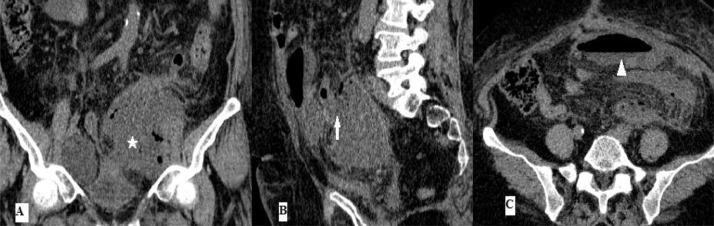

Lymphocele formation following pelvic lymphadenectomy is a well-known complication. In this article, we report a 56 years old female patient with a pelvic infected lymphocele fistulised in the sigmoid discovered in imaging 2 months after pelvic surgery. Lymphocele complications are rare and their diagnosis is based on imaging. However, lymphocele as a potential cause for fistula in the bowel as a particular new case has not been found in literature search.

盆腔淋巴结清扫术后淋巴囊肿形成是一种众所周知的并发症。在本文中,我们报告了一名56岁女性患者,她在盆腔手术后2个月的影像学检查中发现盆腔感染性淋巴囊肿与乙状结肠形成瘘管。淋巴囊肿并发症较为罕见,其诊断基于影像学检查。然而,在文献检索中未发现淋巴囊肿作为肠道瘘管潜在病因这一特殊新病例。